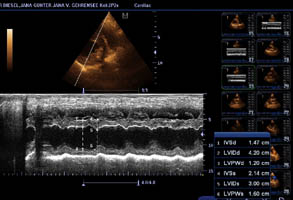

Herzultraschall von Lena vom Gehrensee zur Vermeidung von DCM

Durch Klick auf die Übersicht können die Herzdaten eingesehen werden.

Der Herzcheck ergab keinen Hinweis auf DCM.